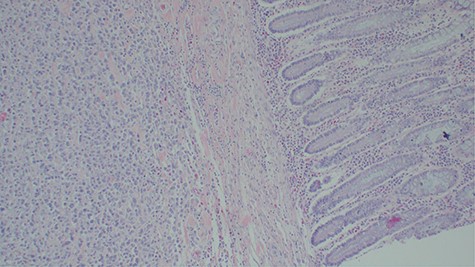

Histopathology of the urinary bladder osteosarcoma metastasizing into the colon. Adjacent normal colon mucosa is seen near the tumor (H&E ×200).